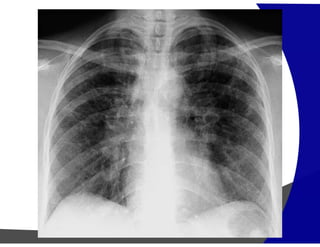

Fibrose Pulmonar

Achados por Imagem

• Raio – X – geralmente normal

Avançada – redução volumétrica e opacidade reticulares

subpleurais com gradiente de apresentação ápico-basais.

• TCAR

Redução volumétrica

Opacidades reticulares subpleurais

Faveolamento (macro)

Bronquiectasias de tração

Gradiente de envolvimento apico-basal

Heterogenicidade espacial e temporal de distribuição

Fibrose Pulmonar Achados porImagem • Raio – X – geralmente normal Avançada – redução volumétrica e opacidade reticulares subpleurais com gradiente de apresentação ápico-basais. • TCAR Redução volumétrica Opacidades reticulares subpleurais Faveolamento (macro) Bronquiectasias de tração Gradiente de envolvimento apico-basal Heterogenicidade espacial e temporal de distribuição